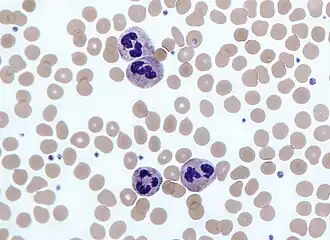

Neutrophils with segmented nuclei surrounded by erythrocytes and platelets. Intra-cellular granules are visible in the cytoplasm (Giemsa stained). | |

Neutrophils are a type of phagocytic white blood cell and part of innate immunity. More specifically, they form the most abundant type of granulocytes and make up 40% to 70% of all white blood cells in humans.[1] Their functions vary in different animals.[2] They are also known as neutrocytes, heterophils or polymorphonuclear leukocytes[3].

The name neutrophil derives from staining characteristics on hematoxylin and eosin (H&E) histological or cytological preparations. Whereas basophilic white blood cells stain dark blue and eosinophilic white blood cells stain bright red, neutrophils stain a neutral pink. Normally, neutrophils contain a nucleus divided into 2–5 lobes.[7]

When adhered to a surface, neutrophil granulocytes have an average diameter of 12–15 micrometers (μm) in peripheral blood smears. In suspension, human neutrophils have an average diameter of 8.85 μm.[15]

With the eosinophil and the basophil, they form the class of polymorphonuclear cells, named for the nucleus' multilobulated shape (as compared to lymphocytes and monocytes, the other types of white cells). The nucleus has a characteristic lobed appearance, the separate lobes connected by chromatin. The nucleolus disappears as the neutrophil matures, which is something that happens in only a few other types of nucleated cells.[16]: 168 Up to 17% of female human neutrophil nuclei have a drumstick-shaped appendage which contains the inactivated X chromosome.[17] In the cytoplasm, the Golgi apparatus is small, mitochondria and ribosomes are sparse, and the rough endoplasmic reticulum is absent.[16]: 170 The cytoplasm also contains about 200 granules, of which a third are azurophilic.[16]: 170

Neutrophils will show increasing segmentation (many segments of the nucleus) as they mature. A normal neutrophil should have 3–5 segments. Hypersegmentation is not normal but occurs in some disorders, most notably vitamin B12 deficiency. This is noted in a manual review of the blood smear and is positive when most or all of the neutrophils have 5 or more segments.